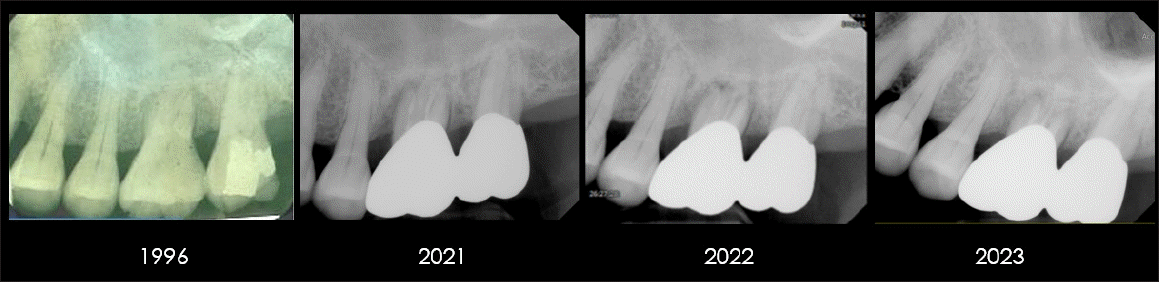

Figure 4.

Serial periapical radiographs of the maxillary anterior region from 2008 to 2022 (year 14). Repeated non-surgical periodontal therapy contributed to relatively stable bone levels around the central incisors. Following a trauma in 2015, apex-involved bone resorption developed in the left central incisor, ultimately leading to extraction and subsequent implant placement.